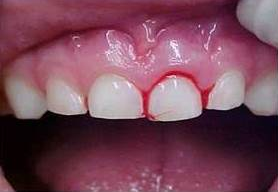

Subluxação dentária

Neste tipo de trauma, o dente apresenta mobilidade aumentada, mas sem deslocamento significativo.

É comum observar sangramento no sulco gengival, o que indica comprometimento do ligamento periodontal.

O tratamento da subluxação inclui:

- Contenção flexível temporária, para estabilizar o dente afetado;

- Cuidados com a higiene bucal, para prevenir infecções secundárias no local do trauma;

- Acompanhamento clínico e radiográfico, para identificar alterações como reabsorção radicular ou necrose pulpar.